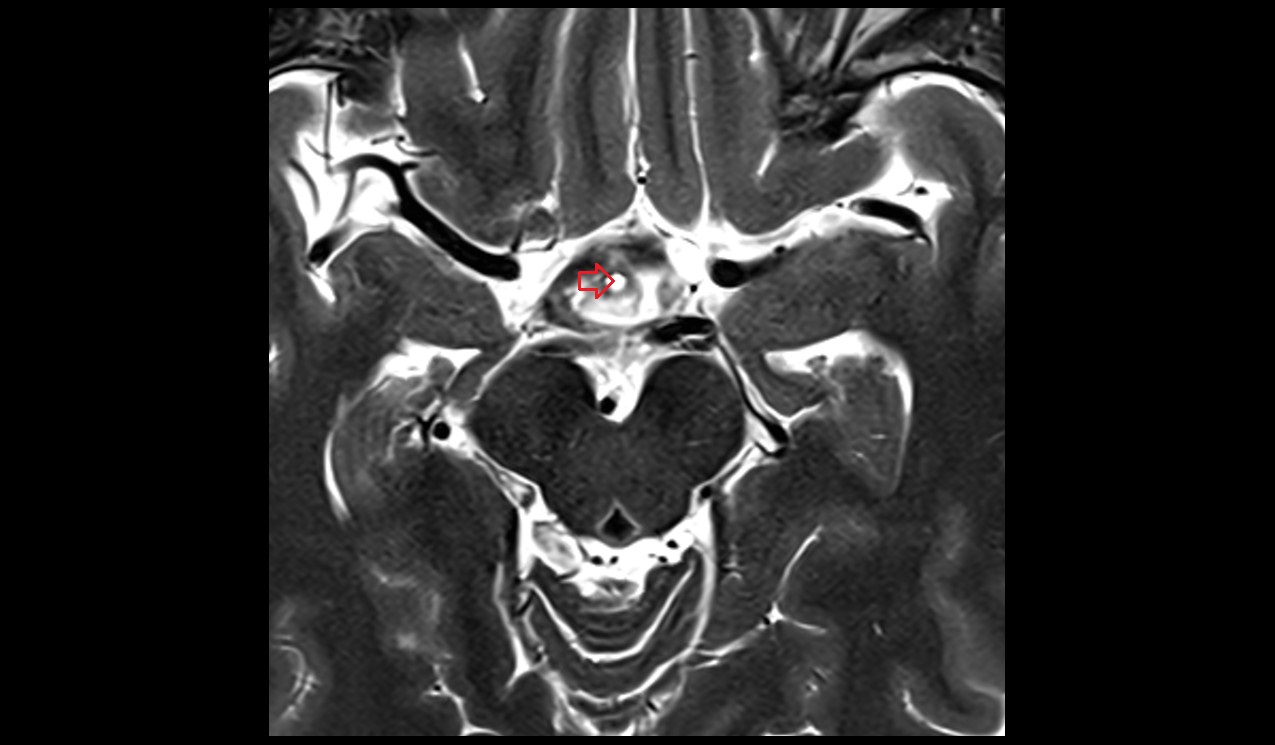

- Meckel’s cave (Trigeminal cave)